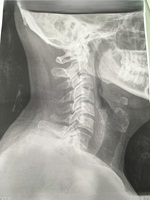

Se aprecia la prótesis de disco colocada entre C5 y C6 | ||||